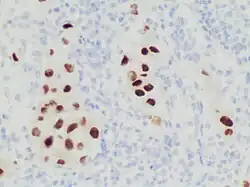

SOX10 is used as an immunohistochemistry marker, being positive in:[11]

- Neuroectodermal neoplasms of neural crest origin, especially:

Immunohistochemistry stain for SOX10 in a poorly differentiated metastatic melanoma to a lymph node, helping in its diagnosis.